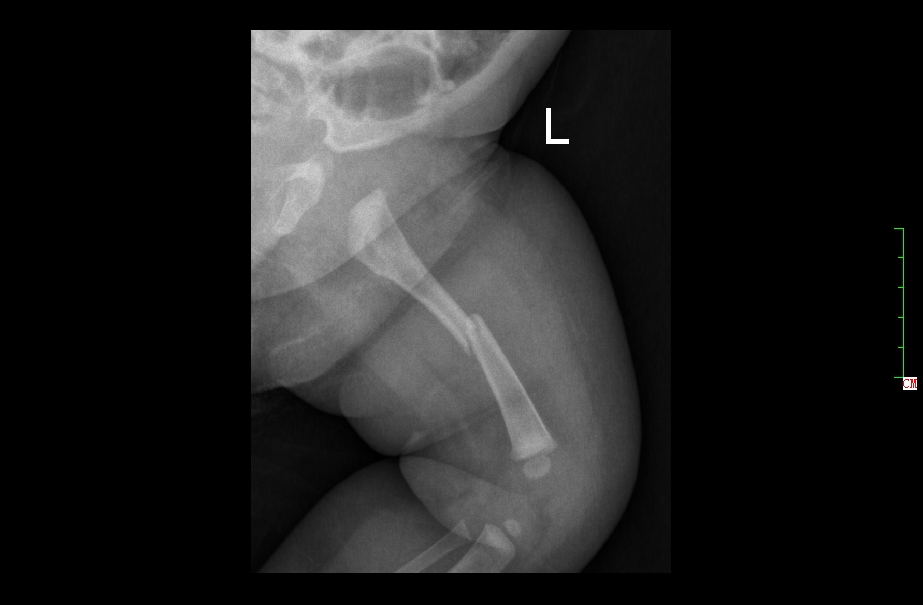

3月女婴股骨骨折正位片

3月女婴股骨骨折侧位片

2 月后复查正位片

2月后复查侧位片

1年后复查正位片,已完全愈合,自行矫形至正常